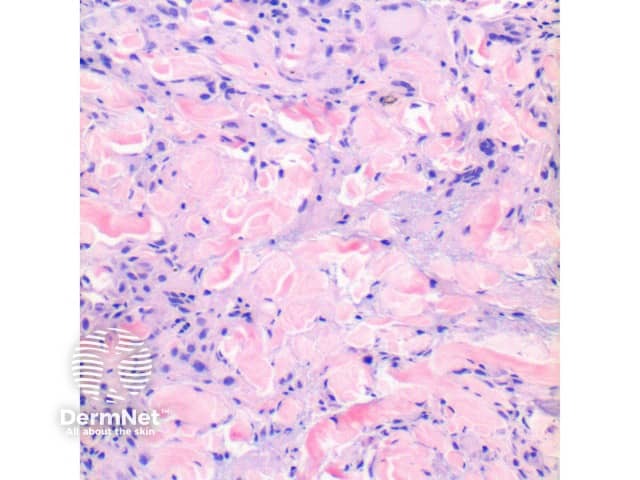

Figure 3